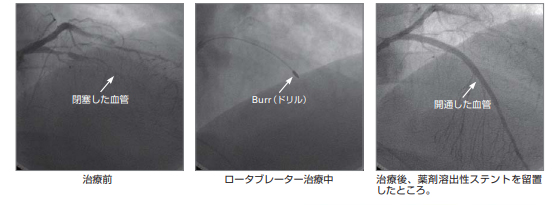

心臓カテーテル/冠動脈形成術 (PCI)

冠動脈に選択的にカテーテルを挿入し、造影剤を注入することにより、冠動脈狭窄に関する詳細な情報を得られます。また、心不全や弁膜症などの重症度を調べるためにも有用な検査です。冠動脈に高度な狭窄を認め、狭心症などの原因になっている場合には、カテーテルを用いてステントを留置するなどの冠動脈形成術(PCI)が可能です。最近では、再狭窄の少ない薬剤溶出性ステントが広く用いられ、良好な成績が得られています。

ロータブレーター

カテーテルの先端に人工ダイヤモンドを装着した装置です。先端チップが高速に回転することで石灰化プラークを切除します。狭窄度の強い石灰化病変に威力を発揮します。